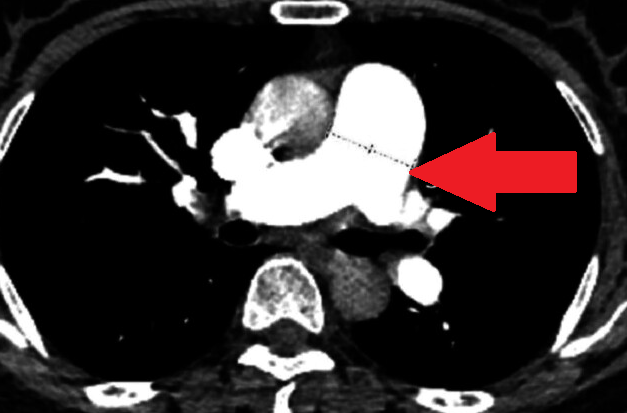

CT αγγειογραφία θώρακα. Κόκκινο βέλος - Έντονη διάταση της πνευμονικής αρτηρίας. Χωρίς ευρήματα πνευμονικής εμβολής (Ευγενική παραχώρηση Dr. V. Penopoulos)